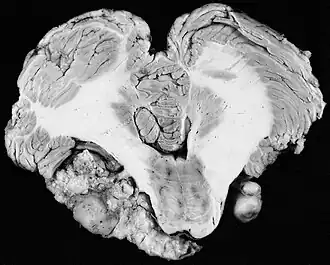

Neurinome bilatéral chez un patient présentant une neurofibromatose de type II